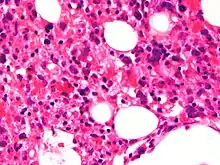

Micrograph showing red blood cells within macrophages. H&E stain.

Light microscopic image of bone marrow showing stromal macrophages containing numerous red blood cells in their cytoplasm